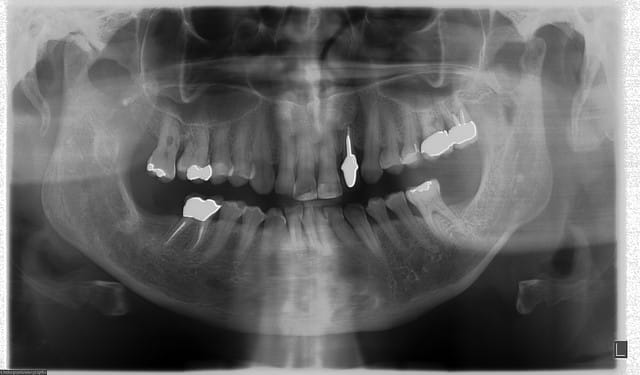

C'est beau mais tu as laissé le nom des patients.

Ma ploc, achtung,comme te le dit tres bien agachon, tes fichiers image ont le nom de tes patients.

Par exemple , il faut TRES VITE que tu renommes dans ton poste de travail (ou l'explorateur de fichiers) , la cephalo numero 1 ( a gauche dans ta presentation) en Tr_Ma_04_10.jpg (comment j'ai su les initiales de ta petite patiente, hein, dis, hein?)

LE NOM DU FICHIER EST EN CLAIR , donc le nom et prenom de ta petite patiente, d'ici 3 jours va etre referencée dans google image. Ca va faire mal, tres mal, tres tres mal! Grouille toi, ploc.

Je t'ai mis ta premiere cephalo plus bas. Le nom du fichier image est codé , tu peux le retrouver facilement plus tard avec une recherche avancée.

IL FAUT FAIRE CELA AVEC TOUTES LES IMAGES.

ok j'essaierai au cab demain,encore que je n'ai rien compris à comment faire(merci adhoc pr plus d'explications step by step en mp) et ai retiré la seule vraie pano de patiente que je veux laisser anonyme mais que j'avais mise parceque je trouvais interessant de voir que mme sur une enfant plus difficile à gérer la qualité ne variait pas

les autres st des panos sur nous pr tester la machine dc on s'en f...! on peut mme considérer que c'est la gloire d'être sur google:)